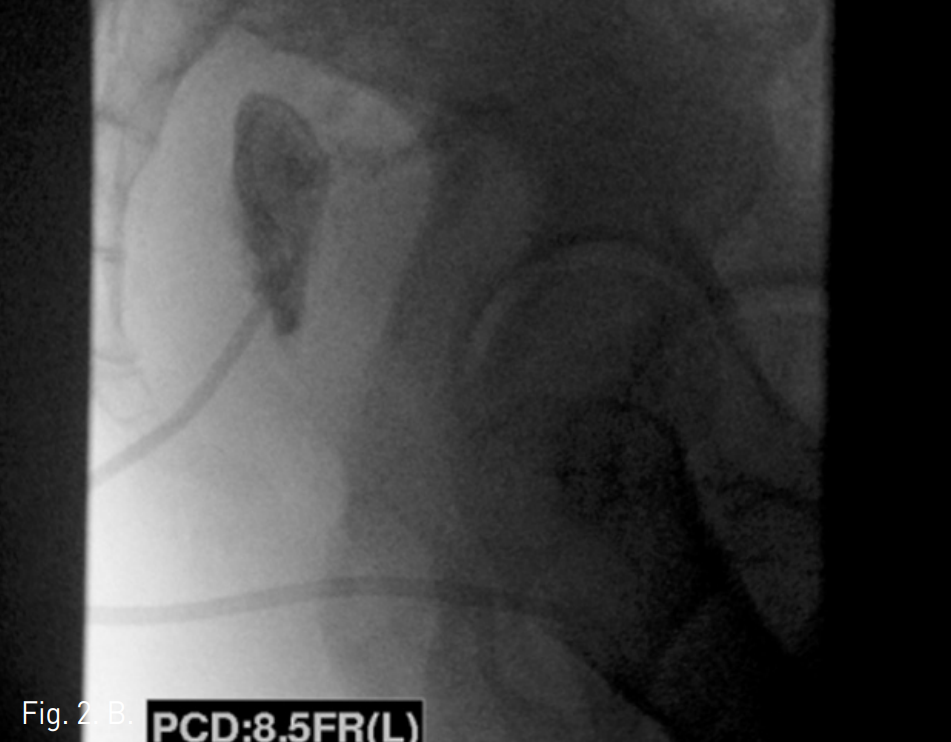

10일 후 추적 CT검사상 천골 전방의 액체저류는 소실되었고, 음영증가의 소견만 관찰되었다(Fig. 3).

Fig. 3

Follow-up enhanced CT axial image shows remained strand-like attenuation at the presacral area (arrows).